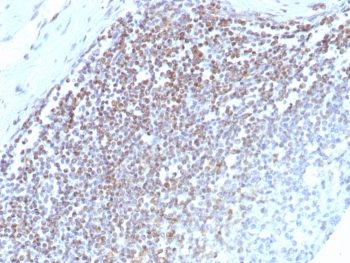

IHC staining of FFPE human spleen tissue with E2F4 antibody (clone E2F4/8984R). HIER: boil tissue sections in pH 9 10mM Tris with 1mM EDTA for 20 min and allow to cool before testing.